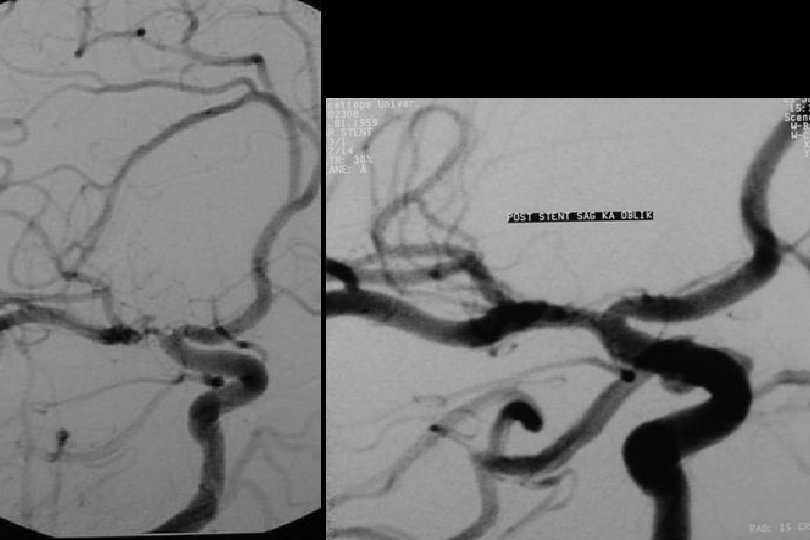

PTA ve Solitaire ile stentleme sonrası

6 ay kontrol